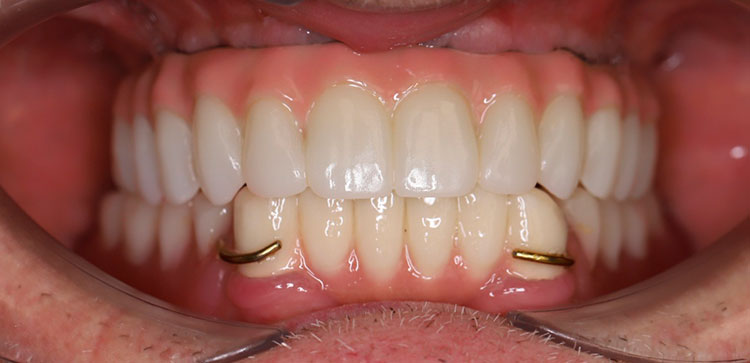

Через 4 месяца пациенту установлен постоянный циркониевый мостовидный протез на титановой балке. Состояние костной ткани хорошее. Состояние десны удовлетворительное, жалоб нет.

Контрольный осмотр через 1 месяц подтвердил успешность данного выбора методики.